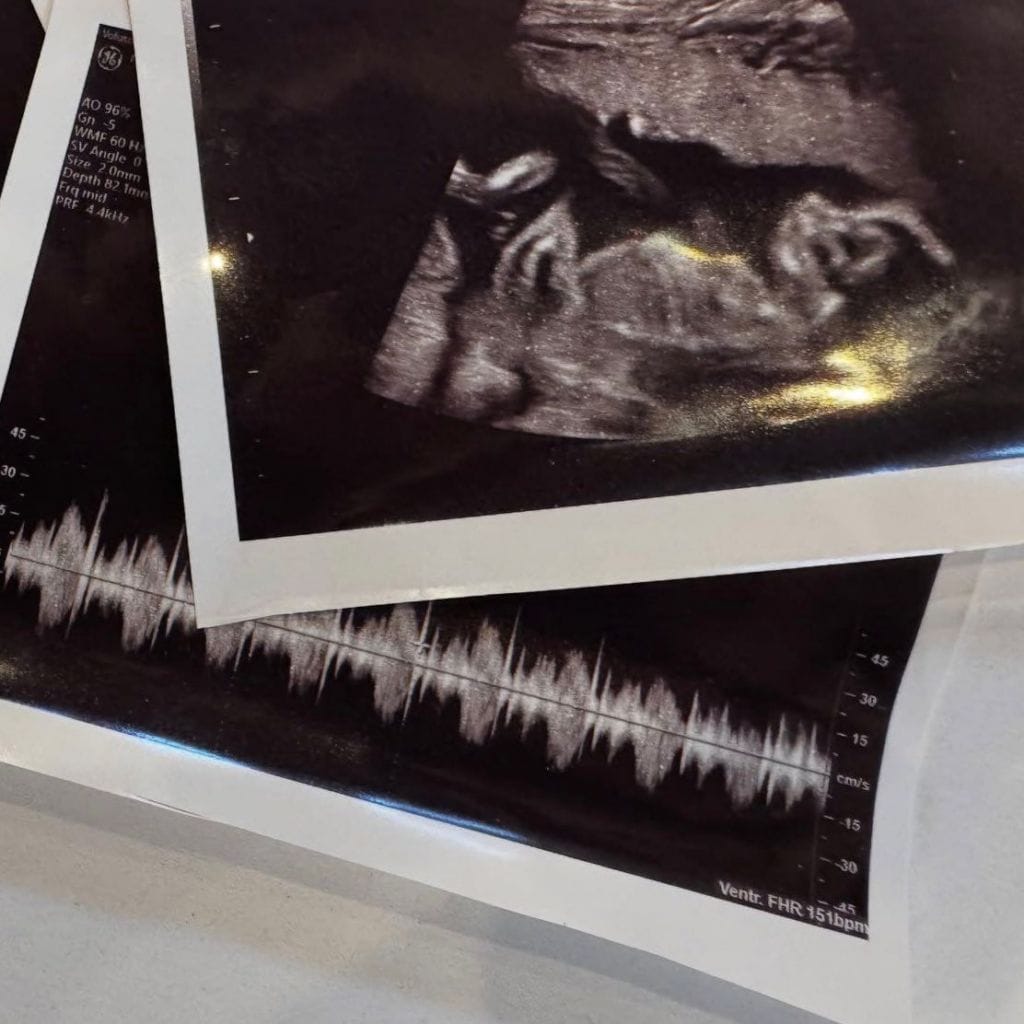

El carrusel también incluyó una ecografía y una ilustración de ambos en versión caricatura, acompañada de la frase: “dun&dun + one”, con la que anunciaron oficialmente la llegada de su bebé. En pocas horas, la publicación superó el millón y medio de “me gusta” y recibió múltiples mensajes de felicitación de seguidores y amigos del medio artístico.